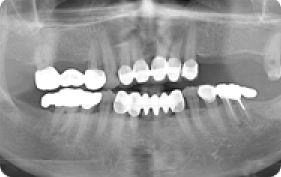

임플란트 상악동거상술 전후사례 | 2020.03.06 |